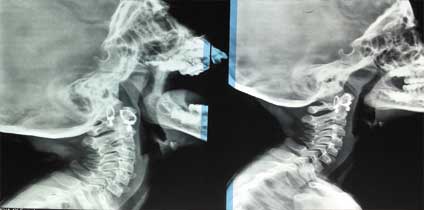

We provide X-Ray services. The technology of X-ray has been constantly improved to make the image quality and diagnostic precision better and more accurate.